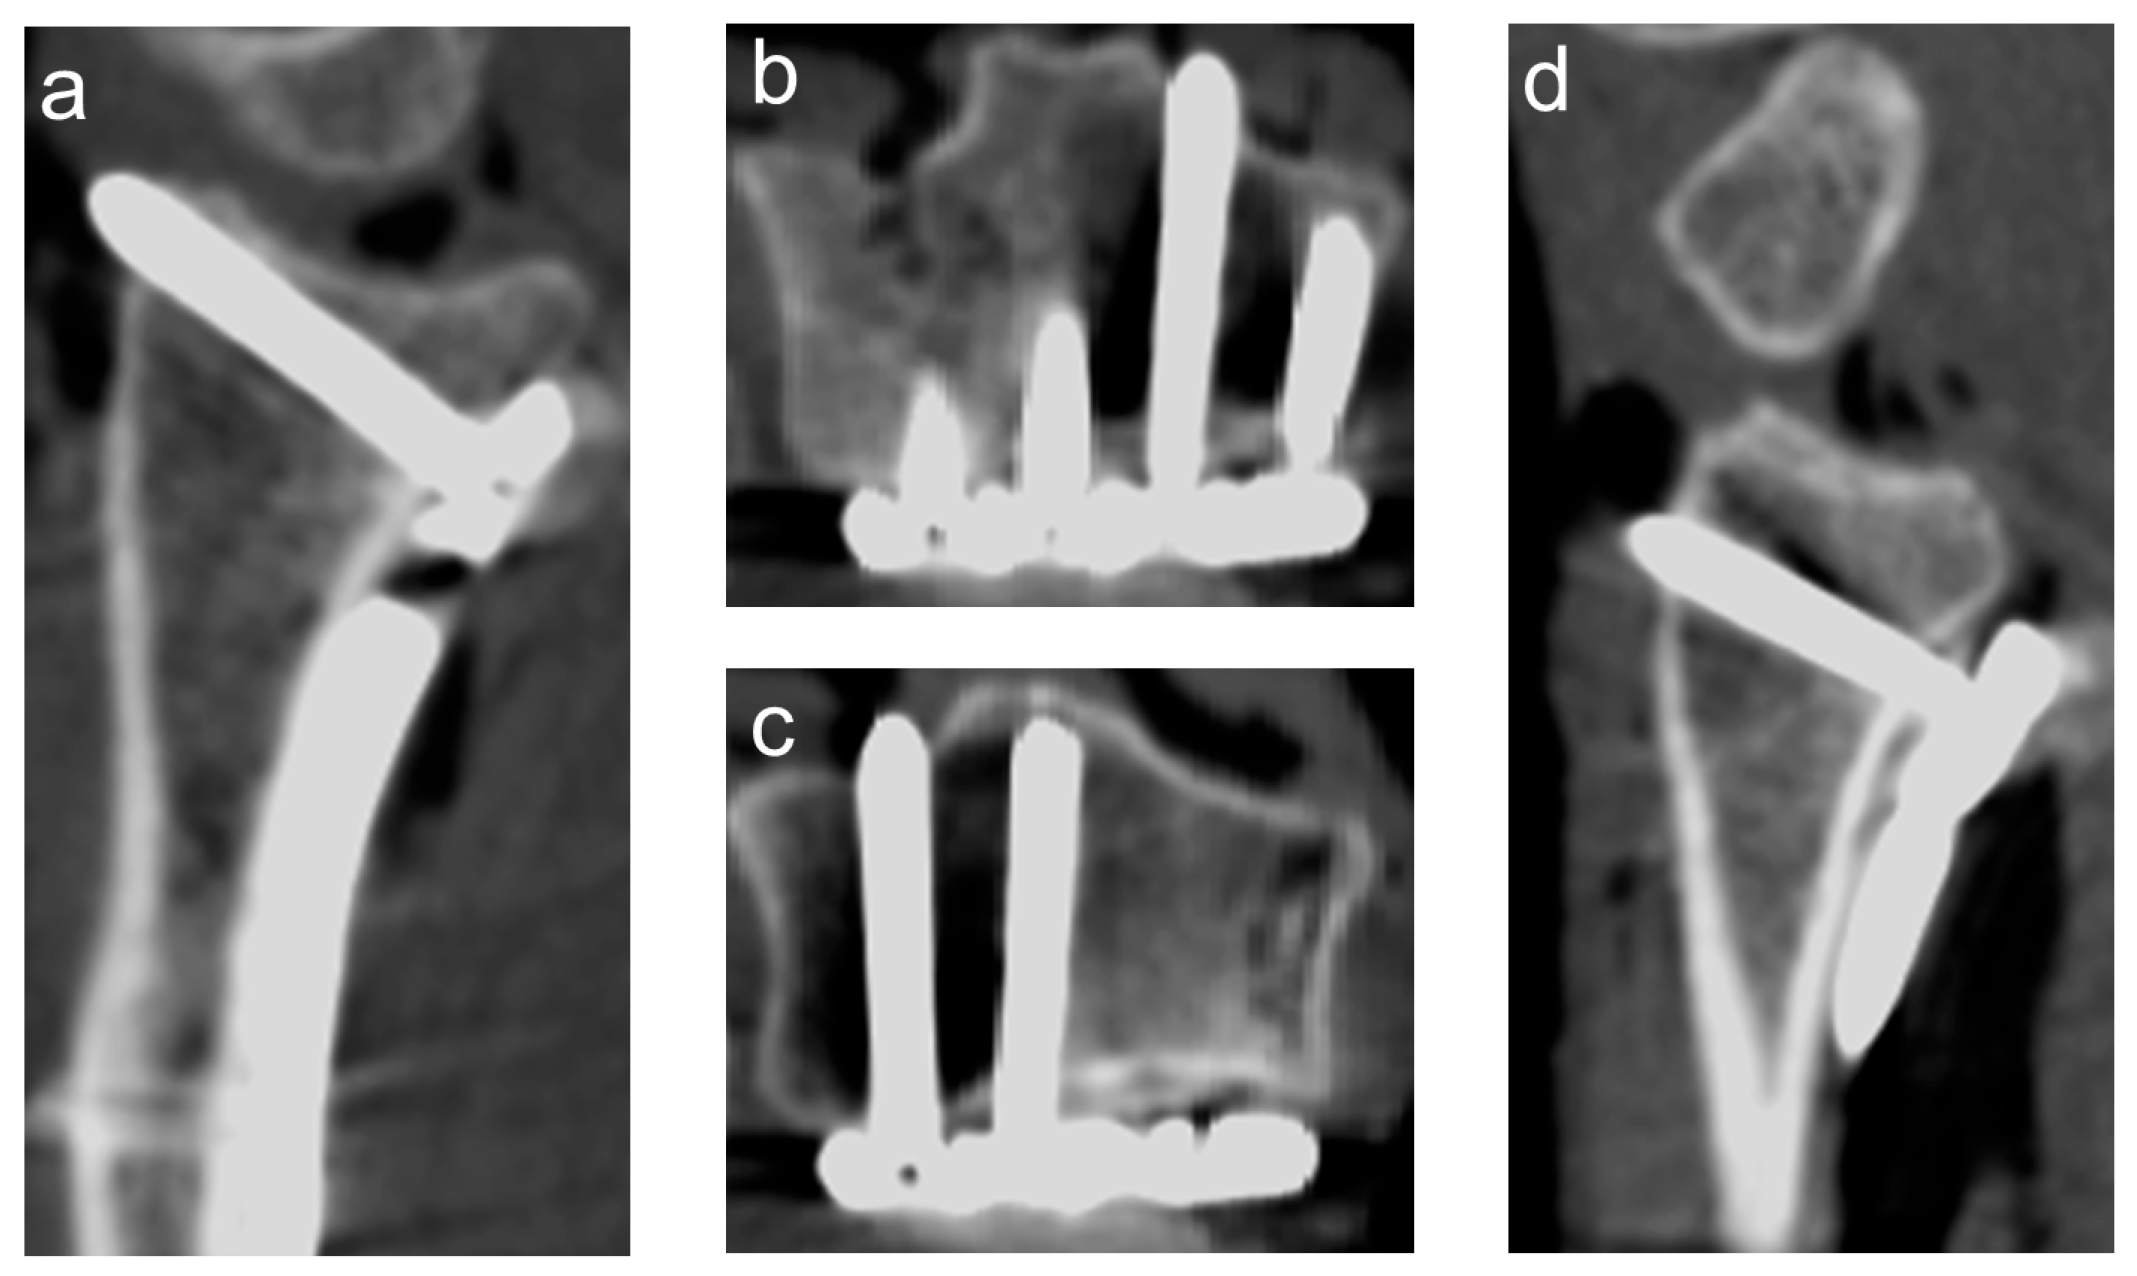

2.3. Dorsal Protrusion

2.4. Intra-Articular Penetration